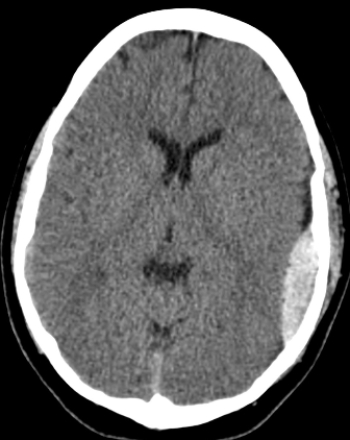

Modalities of Medical Imaging